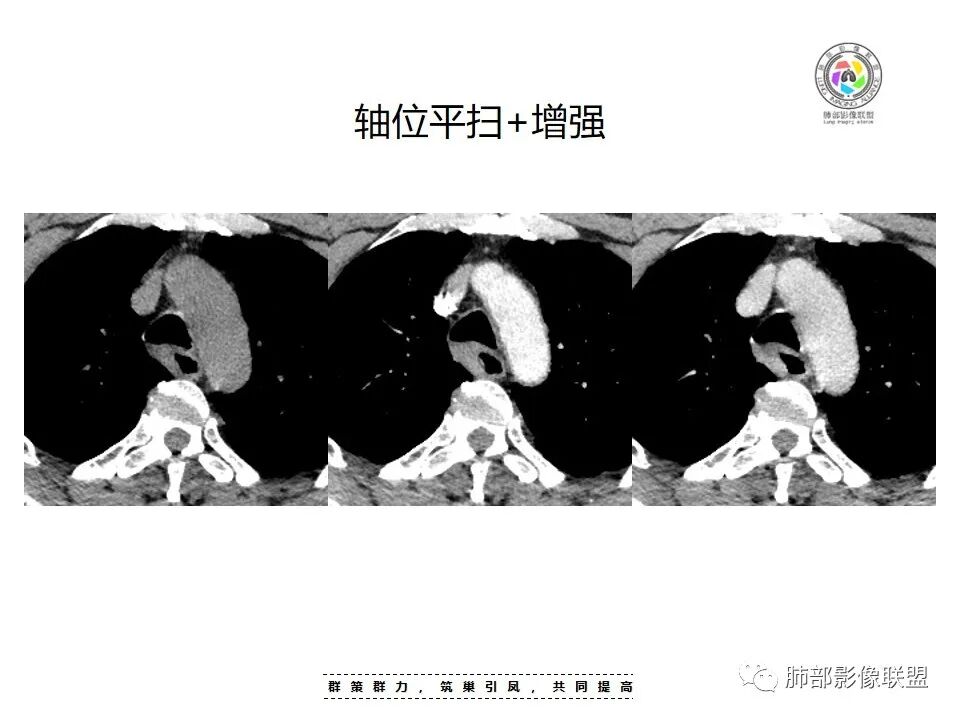

2.定位:右后上纵隔肿块,与食管关系密切,边缘光滑,冠状位显示肿块与食管壁结构相顺延,上下径大于横径,呈现跨管壁内外生长倾向,食管管腔狭窄,而气管腔内未见突入,因此食管来源肿块可能大。

3.结合CT增强图像及食道钡餐影像(管壁整体柔软,粘膜线完整),提示肿块来源于粘膜下。

4.肿块渐进性强化,局部可见低强化区(下图红箭头所示),可以符合神经鞘瘤AB区的影像特点,尽管该部位神经鞘瘤罕见,毕竟食管壁也是有神经走行的,解剖也提示诊断的方向。